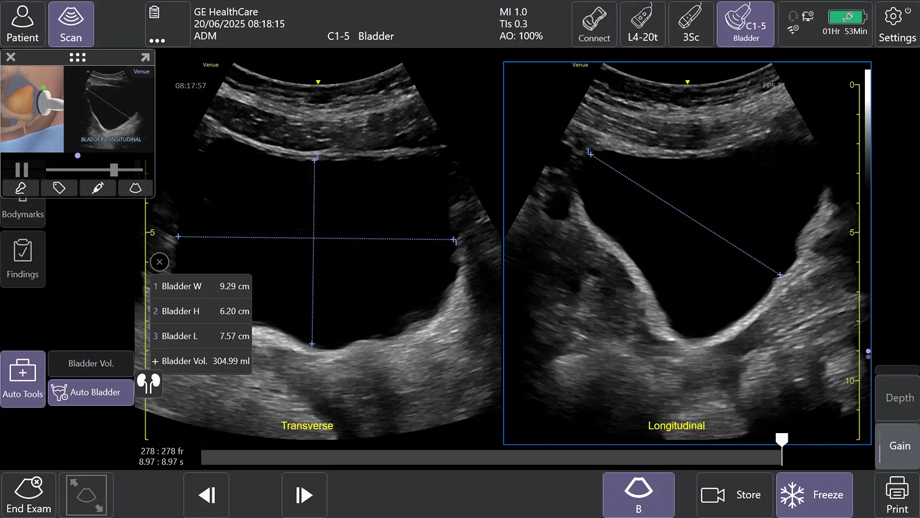

②AIツールAuto Bladder Volume(オートブラッダーボリューム)で膀胱評価を効率化

AIを用いて開発されたAuto Bladder Volumeは、膀胱の容積を半自動で計測するツールである。横断像および縦断像の2方向の画像から、AIが自動的に膀胱形状を認識し容積を算出するため、再現性の高い評価が可能になる。

救急外来や集中治療室、手術後、病棟など様々な場面での活用が想定され、侵襲的な処置を行う事なく迅速かつ効率的な膀胱容積評価が可能となる。